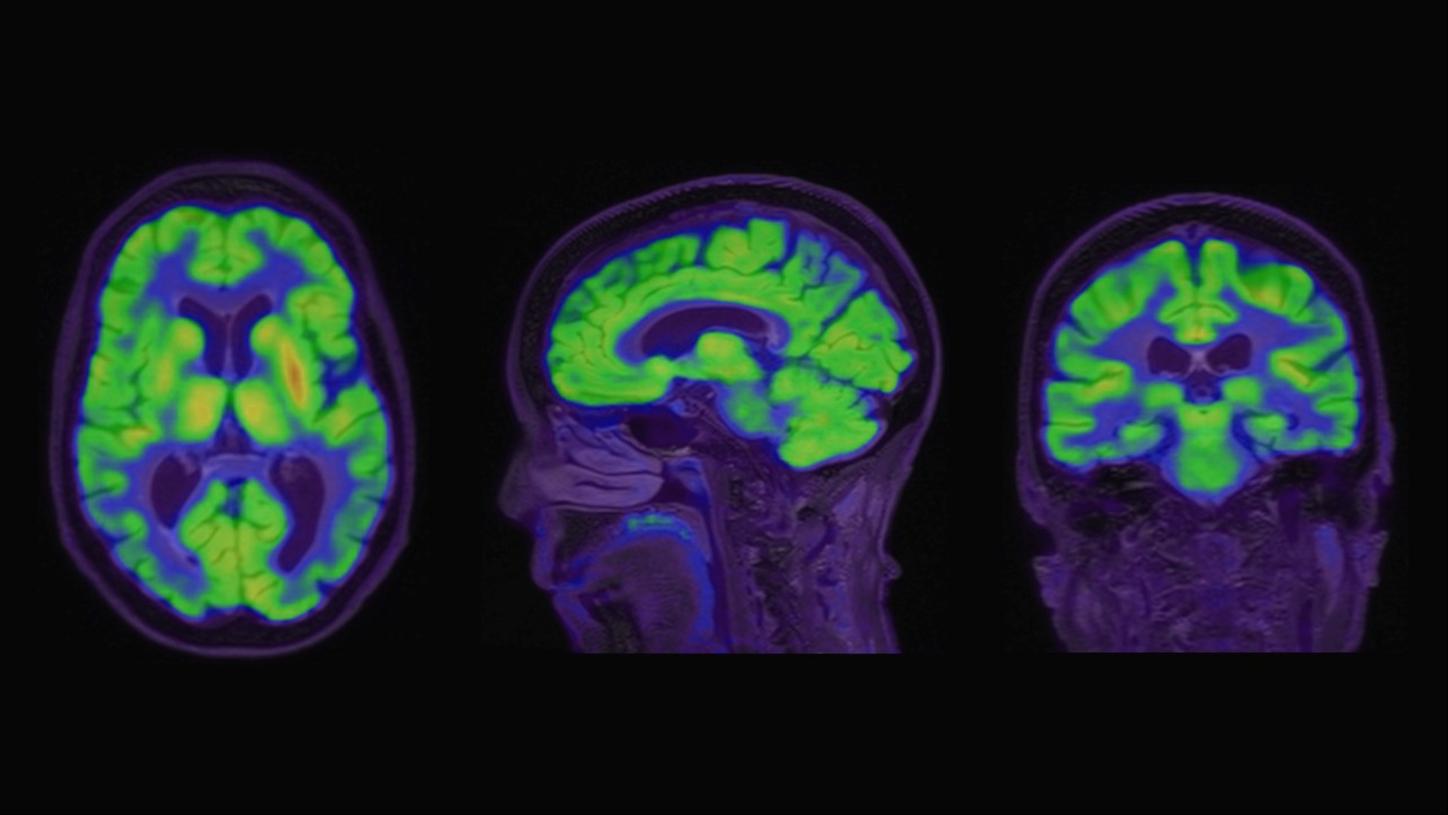

Beta-amyloid PET/CT imaging in the assessment of memory loss and dementia

A 71-year-old male with history of memory loss was referred for PET/CT imaging to evaluate beta-amyloid plaque burden. This case demonstrates the clinical utility of Biograph Vision™ PET/CT imaging and syngo.PET Amyloid Plaque quantification in the evaluation of beta-amyloid plaque density in adult patients with cognitive impairment who are being evaluated for Alzheimer’s disease (AD) and other causes of cognitive decline.